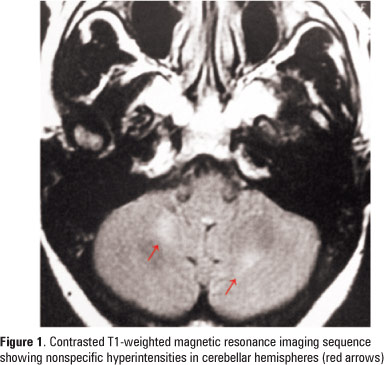

We report the case of a 38-year-old woman with AIDS who developed opsoclonus-myoclonus-ataxia syndrome during a period different from other cases reported in literature. Opsoclonus-myoclonus-ataxia syndrome had already been reported as the initial neurological presentation of AIDS, as well as at the time of HIV-seroconversion and immune reconstitution syndrome. Our case is unique since the patient had an elevated CD4 count and negative viral load in the period when the opsoclonus-myoclonus-ataxia syndrome occurred.

Keywords: Ataxia; Ataxic gait; HIV; Myoclonus; Ocular motility disorders